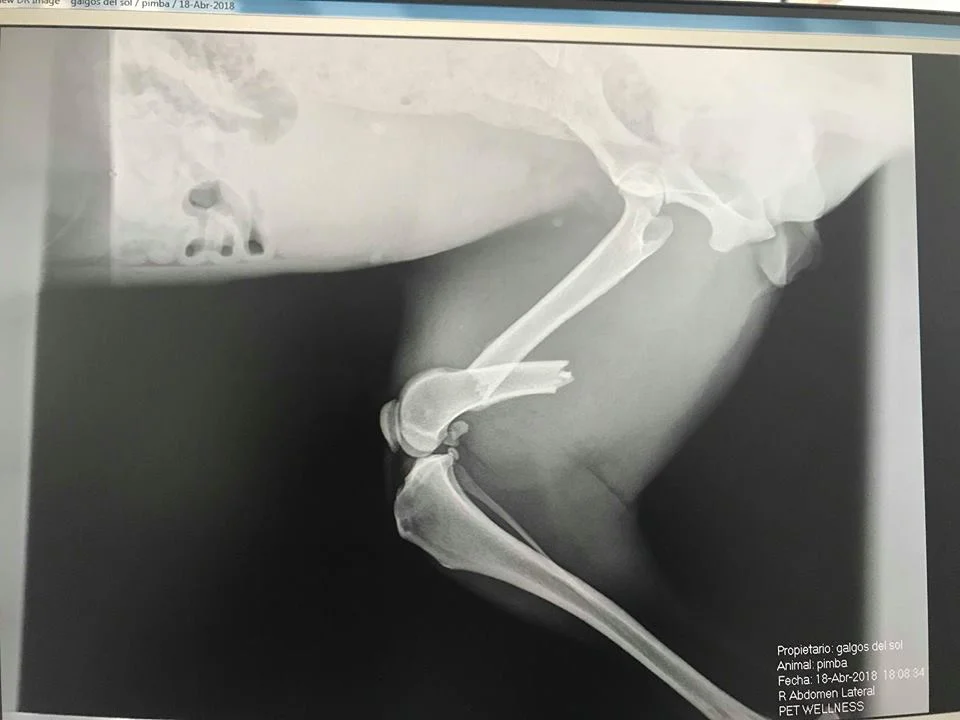

Break in leg

Pretty pod Bimba was seen on the streets for months. After being hit by a car and rescued by a friend of GDS, surgery was required. Bimba has recovered well from her operation. She is mainly coming out on a lead to make sure she doesn’t run too hard on her leg whilst she’s still in the vulnerable stage of recovery. She’s still frightened but the lead walking is really helping her move forward.